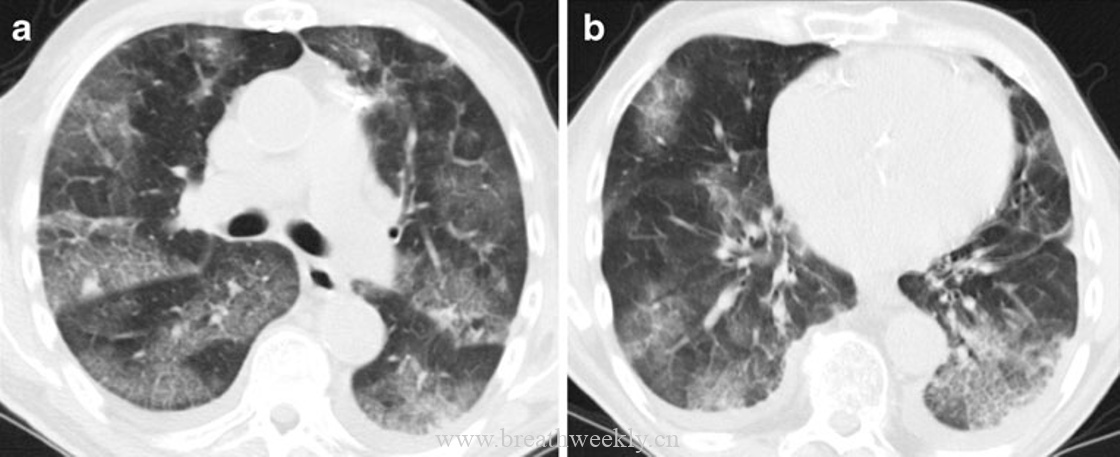

病例1:肺泡蛋白沉积症

临床资料:46岁男性,进行性呼吸困难1周,咳嗽,晨起咳白色粘痰。

影像表现:胸片显示以肺部中央为主的网状影,双肺中央密度增高。CT显示双肺斑片状铺路石征。

病理对照:肺泡内嗜酸性无定形物质,PAS染色阳性,对应表面活性物质缺乏。线状影对应腺泡边缘气腔内物质沉积(腺泡周围型)。

肺泡蛋白沉积症和外源性脂质性肺炎是气腔疾病。在肺泡蛋白沉积症中,气腔被磷脂蛋白样物质填充。CT上肺泡填充导致磨玻璃影,当邻近小叶间隔和肺泡壁的气腔被填充时,形成腺泡周围型。